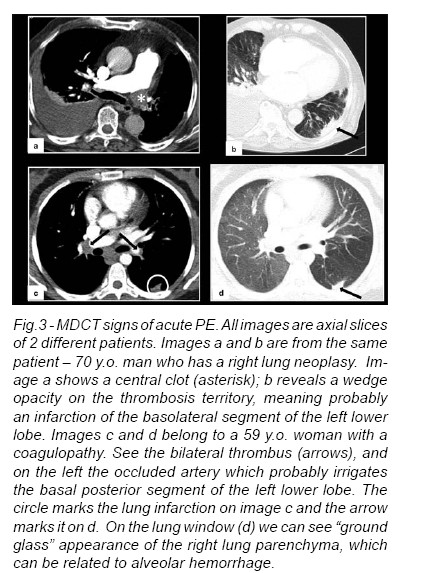

Areas of pulmonary infarction can also be present (Fig.3).